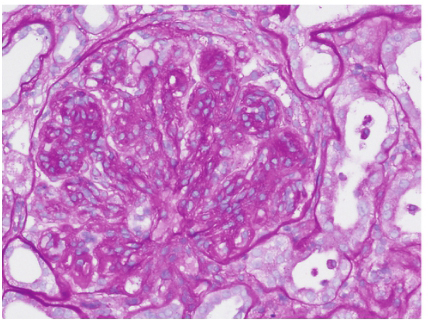

肾活检免疫荧光:IgG(+++),C3(+++),C1q(++),κ(+++),λ(+++),余阴性,系膜区、毛细血管壁颗粒样沉积(图1)。光镜下可见37个肾小球,肾小球系膜细胞和基质重度弥漫增生,广泛插入,肾小球基底膜弥漫不规则增厚,双轨及多轨征形成,系膜区、内皮下嗜复红蛋白沉积,其中2个小细胞性新月体形成;肾小管上皮细胞空泡及颗粒变性,多灶状萎缩;肾间质水肿,多灶状淋巴和单核细胞浸润伴纤维化;小动脉管壁增厚;符合膜增生性肾小球肾炎(图2)。电镜下肾小球系膜细胞和基质重度增生,广泛插入,内皮细胞增生及肿胀,基底膜弥漫不规则增厚,内皮下和系膜区可见电子致密物,上皮足突广泛融合;符合膜增生性肾小球肾炎(图3)。因怀疑HCV相关,进一步进行相关检测:免疫组化染色发现HCVNS3(nucleostemin 3)抗原沿毛细血管壁和系膜区颗粒样沉积,免疫电镜显示HCV-NS3主要位于电子致密物内。因此,该患者的病理诊断符合HCV相关的膜增生性肾小球肾炎。入院后予干扰素抗病毒,依那普利、美托洛尔、叶酸、维生素B12及对症利尿治疗,患者血肌酐渐上升至174μmol/L,伴血钾上升,停用依那普利;加用泼尼松、环磷酰胺治疗,患者尿蛋白渐降至<1g/d,SCr稳定在130μmol/L左右,目前随访1年,病情稳定。

图1 HCV 相关膜增生性肾小球肾炎:IgG(+++),C3(+++),C1q(++),沿系膜区和毛细血管壁团块状和颗粒状沉积(免疫荧光×400)

图2 HCV相关膜增生性肾小球肾炎(PAS×400)